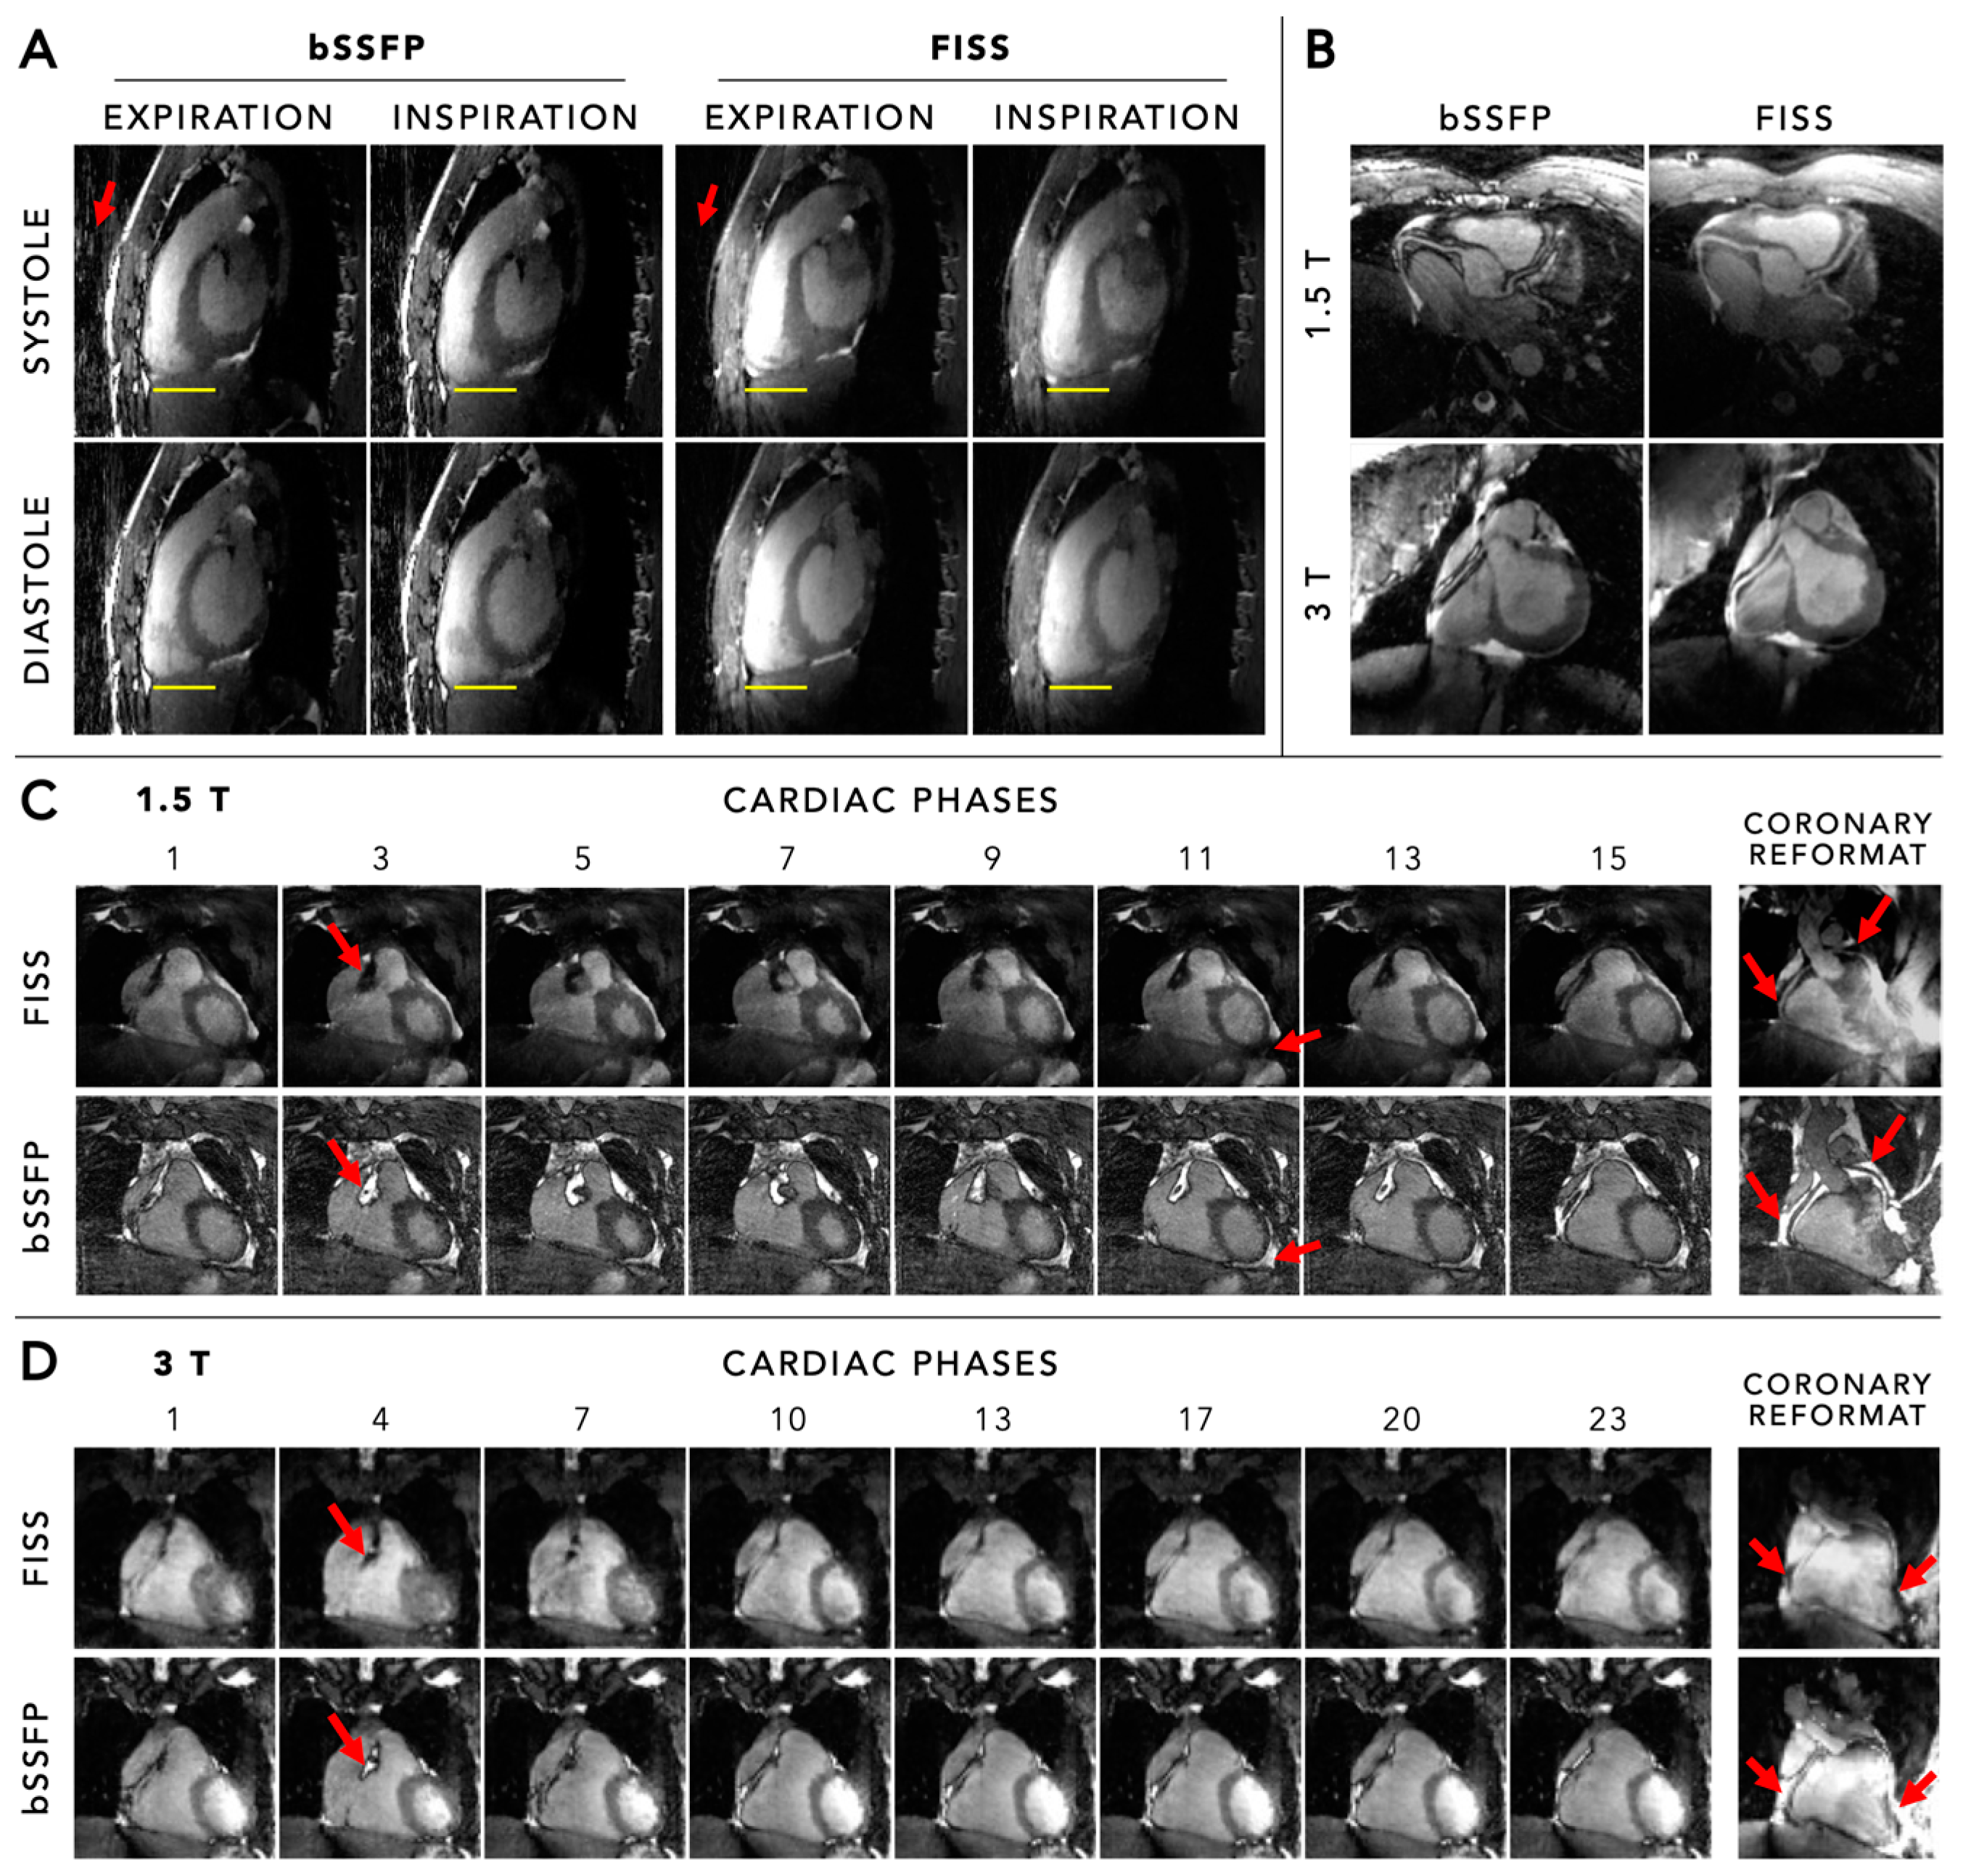

5.1. Anatomical Imaging and Coronary Angiography

6.1. Fat Suppression

6.2. Field Strength Dependency

- Koktzoglou, I.; Edelman, R.R. Radial fast interrupted steady-state (FISS) magnetic resonance imaging. Magn. Reson. Med. 2018, 79, 2077–2086. [Google Scholar] [CrossRef] [PubMed]

- Masala, N.; Bastiaansen, J.A.M.; Di Sopra, L.; Roy, C.W.; Piccini, D.; Yerly, J.; Colotti, R.; Stuber, M. Free-running 5D coronary MR angiography at 1.5T using LIBRE water excitation pulses. Magn. Reson. Med. 2020, 84, 1470–1485. [Google Scholar] [CrossRef] [PubMed]

- Bastiaansen, J.A.M.; Piccini, D.; Di Sopra, L.; Roy, C.W.; Heerfordt, J.; Edelman, R.R.; Koktzoglou, I.; Yerly, J.; Stuber, M. Natively fat-suppressed 5D whole-heart MRI with a radial free-running fast-interrupted steady-state (FISS) sequence at 1.5T and 3T. Magn. Reson Med. 2020, 83, 45–55. [Google Scholar] [CrossRef]